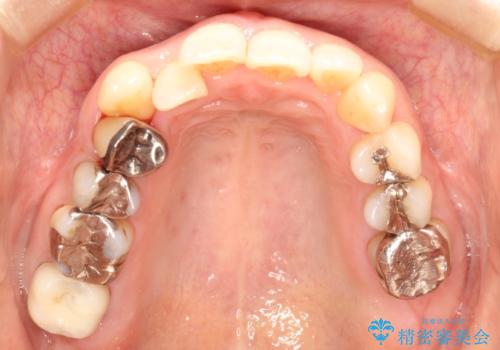

- 右上の八重歯(犬歯の突出)と、それに伴う歯並びのがたつきを主訴にご来院されました。精密検査の結果、八重歯を正しい位置に収めるためのスペースが大幅に不足していることが分かりました。

通常、矯正治療では4番目の歯を抜歯することが多いですが、今回は歯の状態や全体の噛み合わせのバランスを考慮し、右上5番(第二小臼歯)を抜歯してスペースを確保する計画を立案。装置には、周囲に気づかれずに治療を進めたいというご希望に合わせて、透明なマウスピース型のインビザラインを採用しました。

今回の治療では、右上5番の抜歯スペースを活用して八重歯(3番)を後方へ誘導しました。